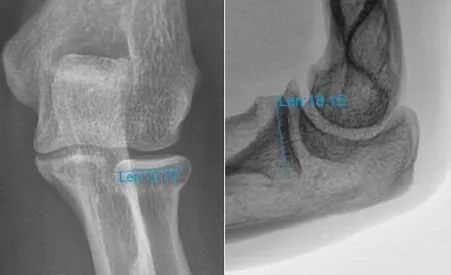

针对该类型骨折,以往常规采取桡骨头切除治疗,但术后常出现因桡骨短缩而导致的肘关节不稳以及下尺桡关节受累情况,后期多疼痛并活动受限。近年来我院上肢骨关节科已成功开展数例人工桡骨头置换手术。故而想到了为患者进行人工桡骨头置换治疗。 ![]() 但是,祸不单行,完善健侧的相关影像资料经测量后发现患者骨骼偏小。常规厂家提供的最小型号桡骨头假体直径为18mm,而患者健侧的桡骨头直径测量不足18mm,且按照该项技术要求,所采用假体直径要比健侧测量值小2mm左右,即直径为16mm假体,术后才能获得满意的活动功能。 针对该困局,患者曾想到放弃对良好功能的追求,行复位内固定的姑息手术。但是我院上肢骨关节科团队仍然为患者深入专研,寻求更好的治疗方案。最后有着多例上肢关节假体置换经验的何晖教授想到了定制一套符合李某自己身体情况的个体化假体进行手术治疗。听到这样的方案,患者及其家属多日的愁眉终于得以舒展。 ![]()